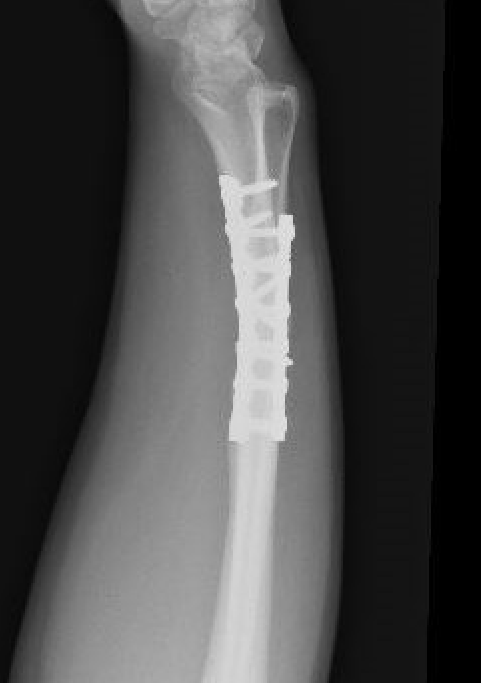

Radial malunion / Non anatomical ORIF of BBFF

Radial malunion after ORIF of BBFF

Etiology

Non operative management of BBFF

Non anatomical ORIF of BBFF

Bone loss radius

Radius short

Lengthening radius difficult

Ulna shortening

Radius angulated / rotated

Radial osteotomy

TFCC repair +/- TFCC reconstruction